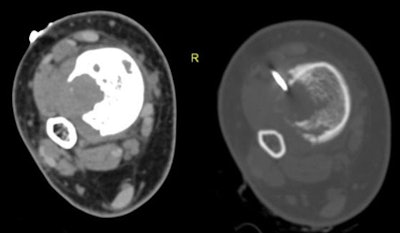

A 15-year-old boy presented with a metaphyseal lucent lesion with well-defined borders that remained quiescent for two years. The patient recently complained of persistent pain and progressive appearance of right ankle swelling. X-ray showed complete changes of the lesion's behavior into a punched-out defect of the distal tibial metadiaphyseal lesion with violated cortex and indeterminate zone of transition, no periosteal reaction or matrix formation were identified. The differential included ruptured chronic bone abscess, Langerhans cell histiocytosis (LCH), and marrow neoplasia. CT-guided biopsy was planned through the large exophytic soft-tissue component seen on CT. This allowed harvesting multiple cores from the main lesion within the bone. The biopsy returned with the result of fibroblastic osteosarcoma. Above, x-ray distal both leg bones and ankle in anteroposterior (left image) and lateral (right image) projections showing distal tibial metadiaphyseal cortical and eccentric lesion with cortical defect and indeterminate medial margin. Neither periosteal reaction nor matrix formations are recognized. Below, axial CT scans of the distal tibial lesion in soft-tissue window setting prior to start of the CT-guided procedure (left image) and bone window setting during the procedure (image at right). All images courtesy of Dr. Mohamed Ragab Nouh.